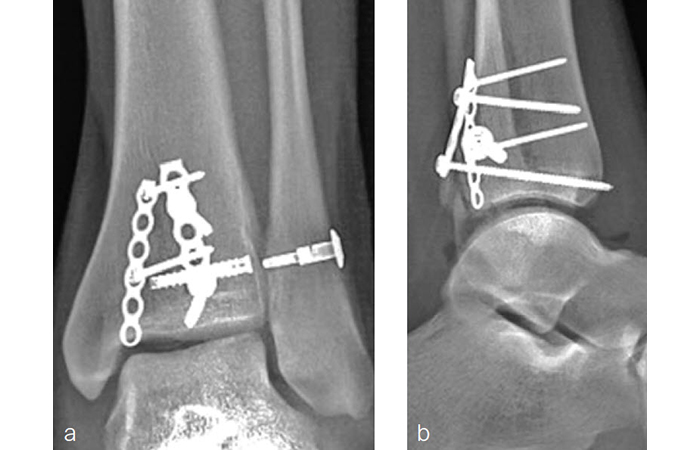

A 27-year-old man fell from a ladder sustaining a proximal fibula fracture (Fig 1) with a multipart posterior malleolar fracture (Fig 2). The patient was treated operatively with direct reduction and plate fixation of the posterior malleolar components. Intraoperative testing demonstrated continued syndesmotic instability requiring fixation (Fig 3). The syndesmosis was reduced in direct fashion and stabilized with a provisional K-wire and clamp before insertion of a FIBULINK Implant (Fig 4).

The patient healed (Fig 5) and returned to preoperative function.